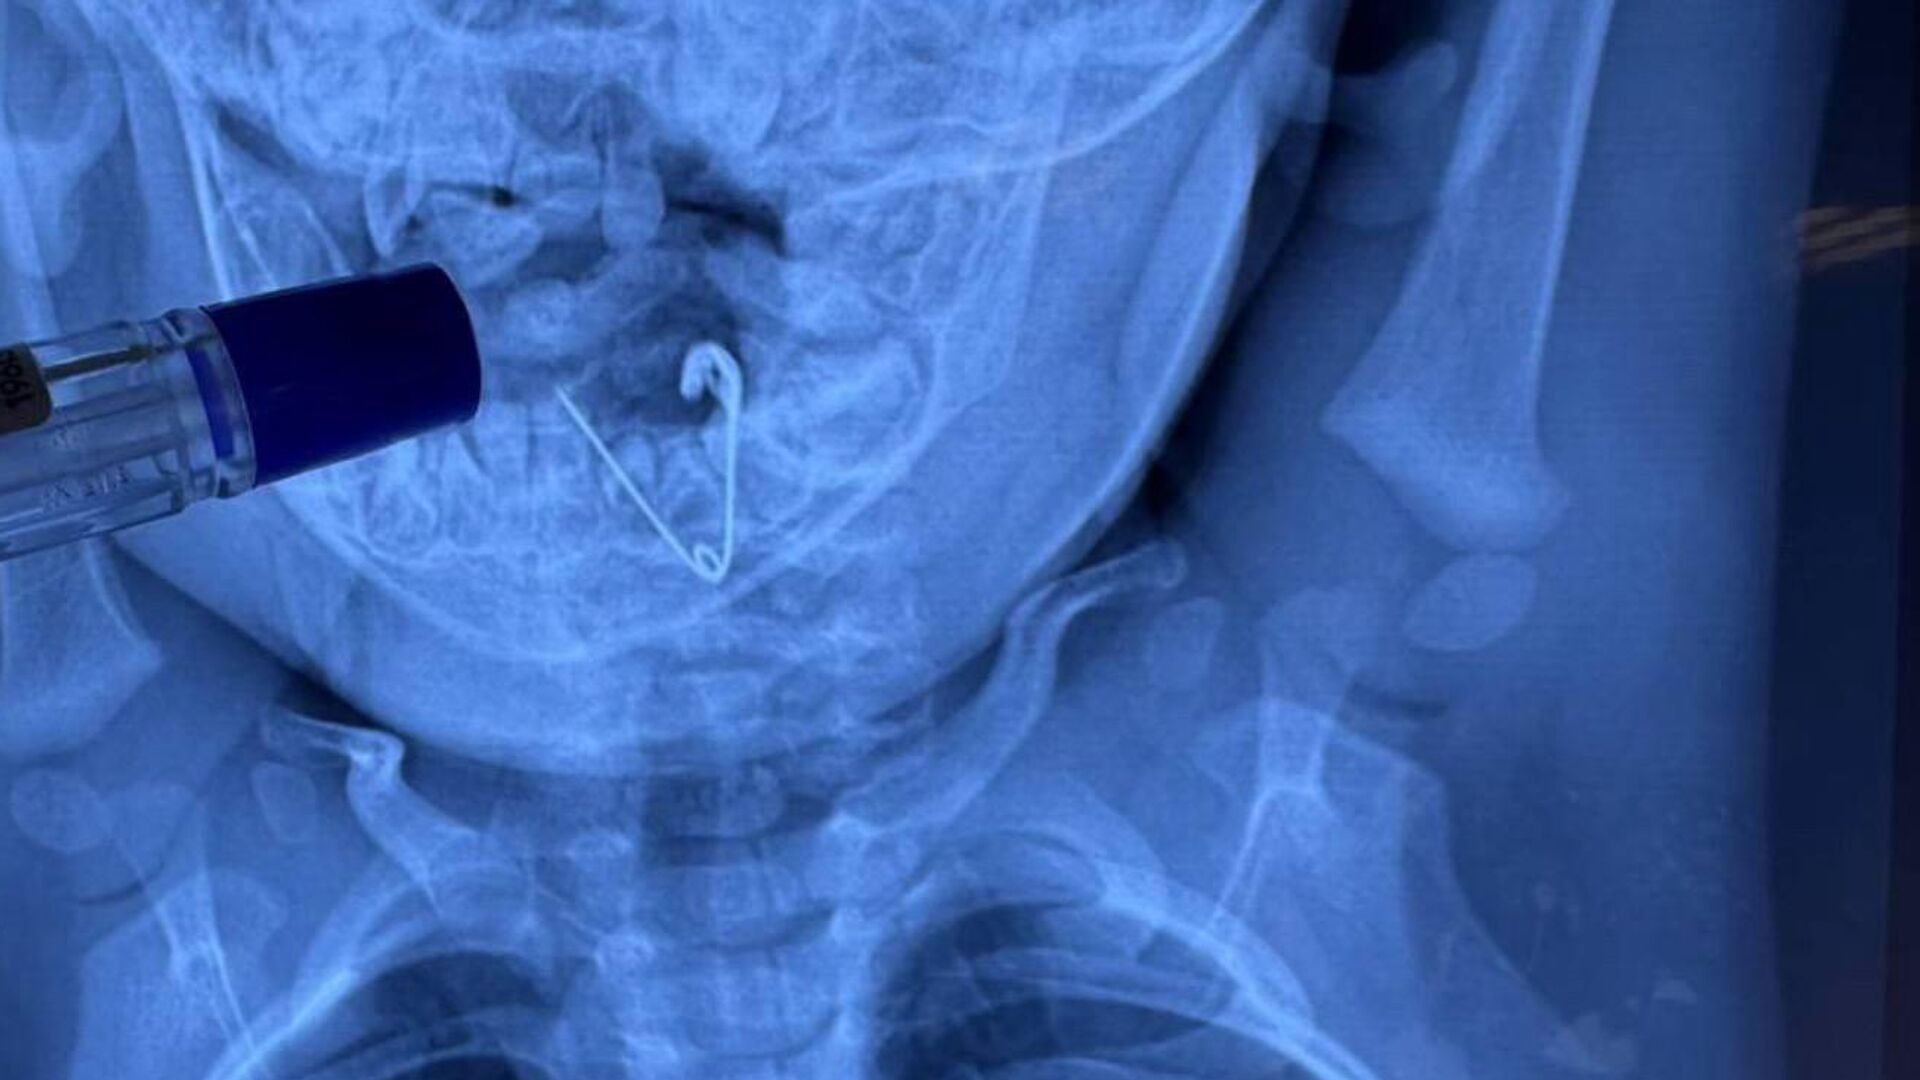

НАЛЬЧИК, 30 окт — РИА Новости. Медики Республиканского центра высоких медицинских технологий в Кабардино-Балкарии впервые на Северном Кавказе применили инновационный метод и спасли пациента с тяжелым тромбозом от ампутации ноги, сообщил региональный Минздрав.

Как рассказали в ведомстве, 66-летнему мужчине с тромбозом правой поверхностной бедренной артерии грозила потеря конечности. С помощью современной ультразвуковой технологии EKOS ему провели локальный акустический тромболизис.

Пациенту через специальный катетер ввели тромболитик — препарат, растворяющий сгусток крови. В то же время катетер генерировал низкоинтенсивные ультразвуковые волны, которые способствовали разрушению тромба и усиливали проникновение препарата. Продолжительность терапии составила шесть часов. После успешного восстановления кровотока врачи провели стентирование артерии для закрепления результата и профилактики повторного сужения сосуда.